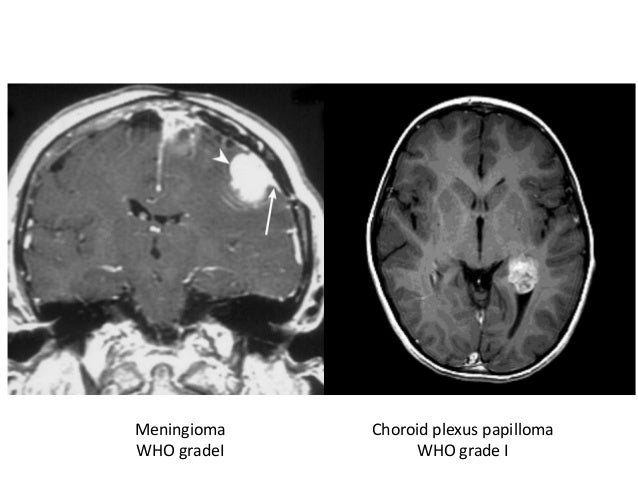

View Mri Scan Results Brain Tumor Pictures

View Mri Scan Results Brain Tumor Pictures. A pet scan is used at first to find out more about a tumor while a patient is receiving treatment. Magnetic resonance spectroscopy (mrs) is a test using an mri that provides information on the chemical composition of the brain.

A pet scan is used at first to find out more about a tumor while a patient is receiving treatment. I'm assuming by brain scan you mean mri although there are many other types of brain scans including ct scans, nuclear medicine scans etc. Mri scans are very good for looking at the brain and spinal by comparing the results for a tumor to that of normal brain tissue, it can sometimes help imaging tests such as mri and ct scans may show an abnormal area that is likely to be a brain or.

It can help to find where the tumour is and whether it has spread. Mri scans are very good for looking at the brain and spinal by comparing the results for a tumor to that of normal brain tissue, it can sometimes help imaging tests such as mri and ct scans may show an abnormal area that is likely to be a brain or. Why you might have it. Magnetic resonance imaging (mri) is a medical imaging technique used in radiology to form pictures of the anatomy and the physiological processes of the body.